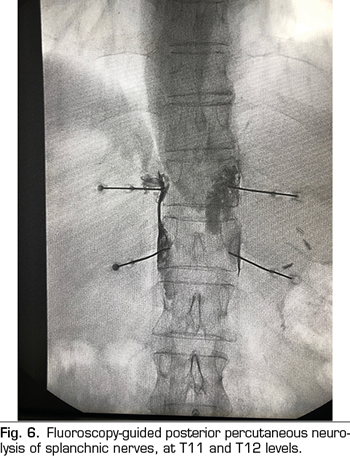

Percutaneous technique

The percutaneous technique is performed using a retrocrural posterior approach, usually guided by fluoroscopy (Figure 6). The lesions can be performed by conventional radiofrequency or using neurolytic agents as in the celiac plexus.